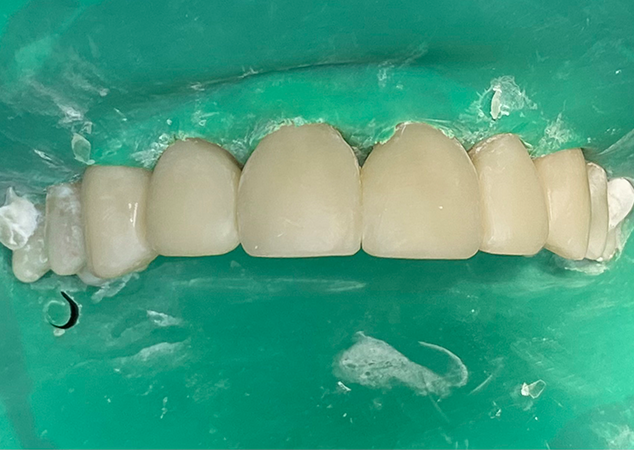

FIG. 11

Immédiatement après l'opération.